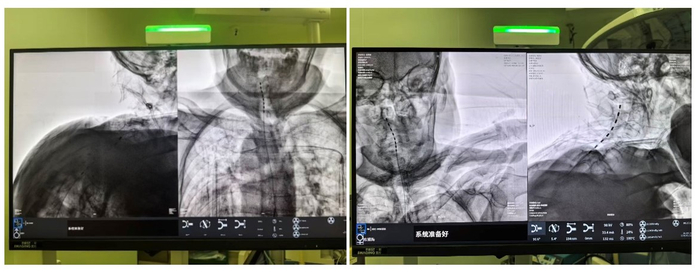

C臂透视示术中电刺激已成功置入。手术在局麻下进行,老人全程清醒。术中,当电极启动测试时,陈奶奶激动地反馈:“麻到了!颈椎和肩胛都不痛了!”这种即时反馈确保了电极能够百分百覆盖痛区。术后一周,两位老人的疼痛视觉模拟评分(VAS,0分为无痛,10分为剧痛)从术前的8-9分骤降至2-3分,睡眠质量和情绪状态得到了质的改善。胡蓉教授介绍,脊髓电刺激术尤其适合高龄疼痛患者,主要具有三大优势:一是微创安全,手术仅需穿刺,创口小,避免全麻对全身系统的干扰;二是个体化管理,患者可通过体外遥控器自主调节刺激强度,实现“我的疼痛我做主”;三是适应证较广,除带状疱疹后神经痛外,也适用于腰椎术后疼痛综合征、复杂性区域疼痛综合征、糖尿病周围神经病变痛等多种顽固性慢性疼痛。目前,汪爷爷已康复出院,陈奶奶也在稳步恢复中。湘雅三医院疼痛科作为湖南省临床重点专科,拥有包括国家杰青、博导、教授在内的顶尖专家团队,在神经调控与微创介入领域持续创新,致力于帮助更多患者,尤其是高龄患者,摆脱顽固疼痛的束缚,重拾生活尊严与笑容。